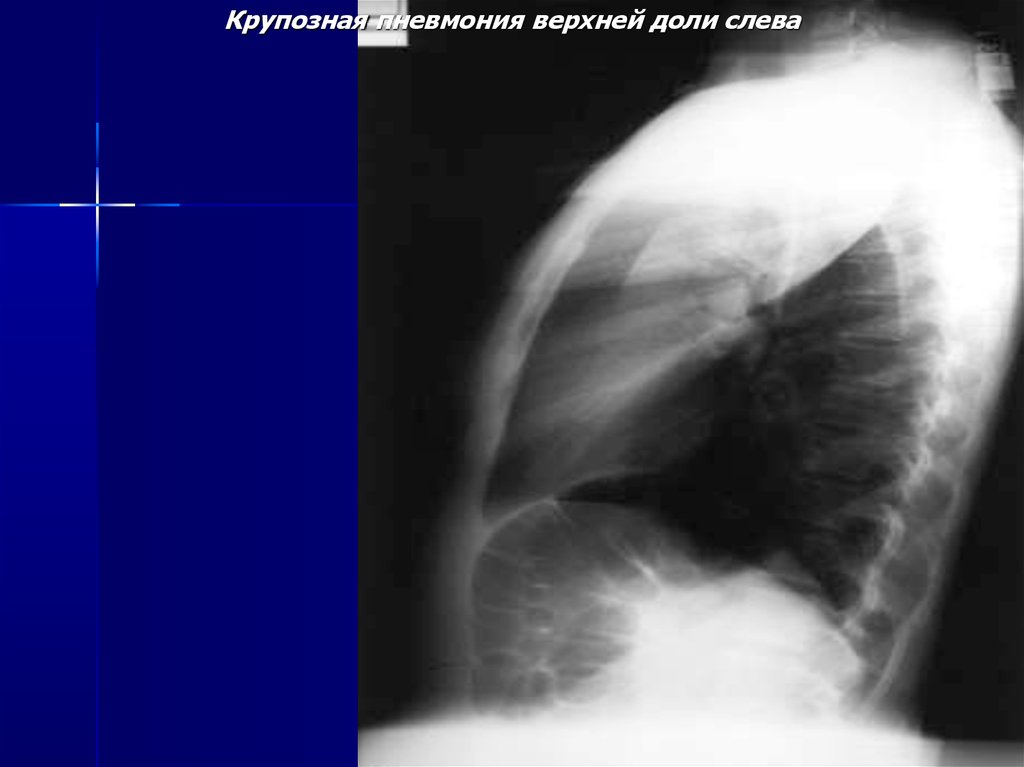

Крупозная пневмония верхней доли слева